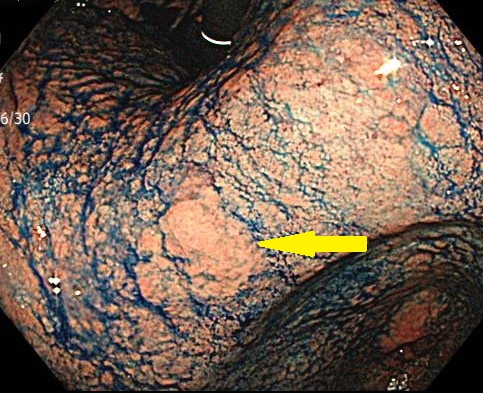

大腸カメラ

「検査について」では、胃カメラ・大腸カメラの目的、受け方、準備や食事制限、鎮静の選び方までをやさしく解説。定期的な内視鏡検査が咽頭・食道・胃・大腸のがんの早期発見や予防に役立つポイントも紹介します。はじめての方へ、当日の流れや受診の目安、よくある不安への答えもまとめます。

たった5分の胃カメラで命を救う 食道・胃・十二指腸まで「早期発見」を最短距離で

「癌について」では、内視鏡専門クリニックの視点から、胃がんと近年死亡者が増える大腸がんを中心に解説。リスク要因、予防、症状の見極め、胃カメラ・大腸カメラでの早期発見の重要性を、最新エビデンスと症例を交えてわかりやすく紹介します。検診の受け方や間隔も具体的に案内し、“見逃さない”ためのポイントなどを解説します。